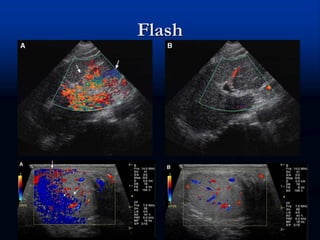

Flash

 Banda de cor produzida por tecidos em

movimento

 Alças intestinais, diafragma, movimento do

transdutor, etc.

Flash  Banda decor produzida por tecidos em movimento  Alças intestinais, diafragma, movimento do transdutor, etc.

• #65 Flash artifact: patient motion. (A) Longitudinal CDUS through the left lobe of liver with flash artifact (arrows) produced by respiratory motion. (B) Longitudinal CDUS with no motion shows normal vascular flow with no artifact. Flash artifact: transducer motion. (A) Longitudinal CDUS of the left testis with flash artifact (arrows) caused by transducer motion. (B) Without motion, normal testicular vessels are easily identified.